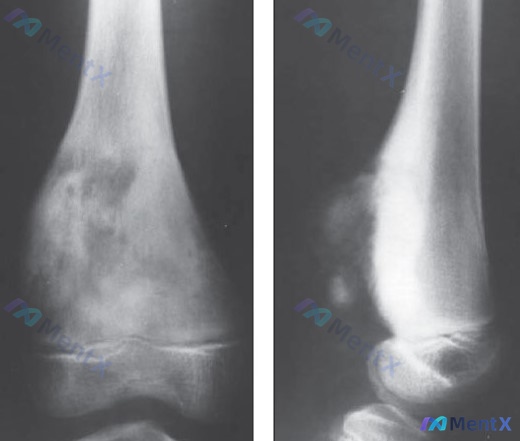

整理了一份青少年骨肿瘤病例资料,有几个关键点值得讨论。 患者信息:13 岁男性。 主诉:几个月内右膝进行性疼痛。 体征:右股骨远端肿胀和压痛。 影像表现:股骨远端干骺端可见明显的骨质结构改变。正位片显示不均匀密度增高影,呈片状、云雾状,边界相对模糊。侧位片显示病变区域向骨表面外侧突起,骨皮质轮廓不连...